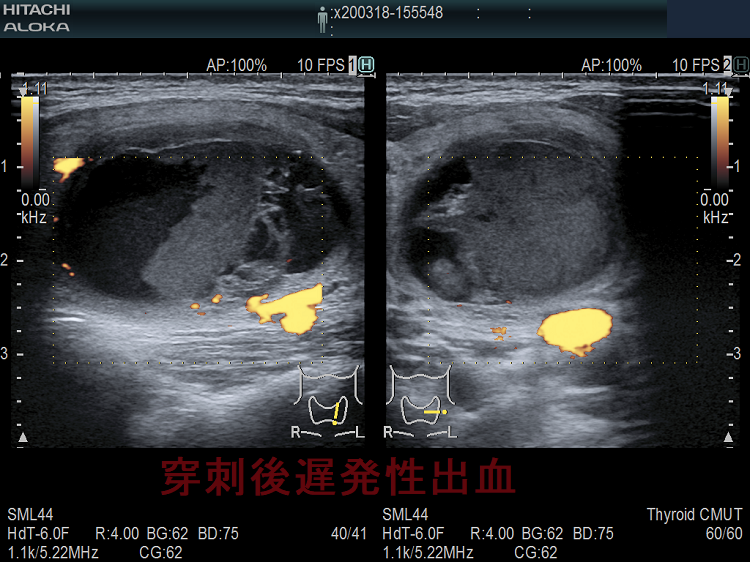

特に、のう胞性腫瘍(嚢胞性腫瘍)の排液を行う場合、粘稠な液が多いため太い針(21G)を使用します(輸血用の18G針を使う施設もありました)。当然、刺し口も大きくなるため、出血の危険が増します[のう胞内出血(嚢胞内出血)]。また、穿刺当日は何もなくても、塞がった刺し口が完全に固まるまでは脆弱なため、無理な力が掛かると、穿刺2週間後でも出血をおこします(穿刺後遅発性出血)。

甲状腺穿刺細胞診後の巨大血腫・活動性出血

(報告例)甲状腺穿刺細胞診から3時間後、重度の呼吸困難をきたし、気管内挿管。造影CTで気管を圧排する巨大血腫(上の写真左)と、活動性出血を示唆する造影剤の漏れ(Extravasation)(上の写真右)を確認。